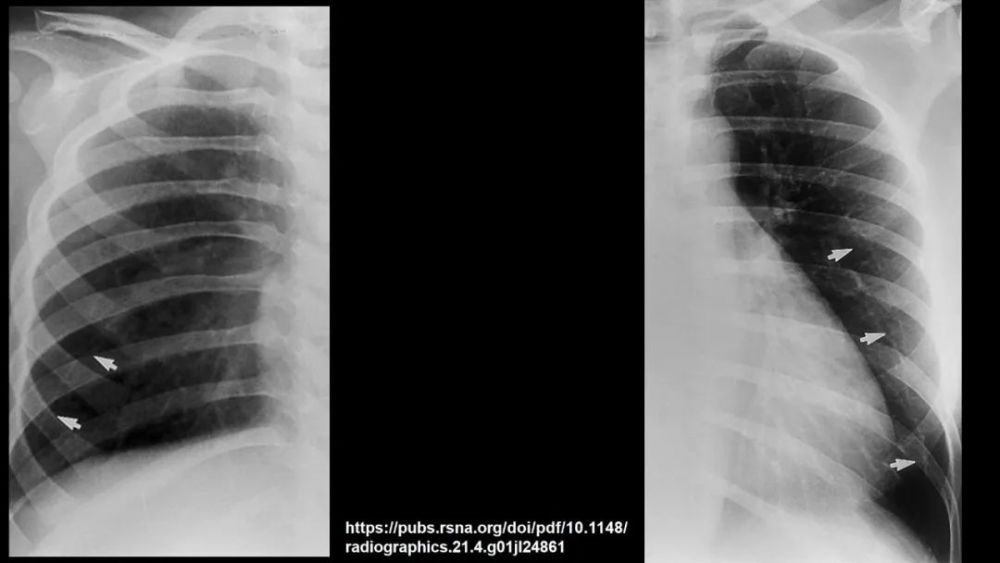

Inferior accessory fissure

Twining’s line , 分隔下叶的内侧基底段

CT上的检出率:12% , 前位胸片显示率:5~8%R:L=5:1;多为不完整的 , 0.5~2cm